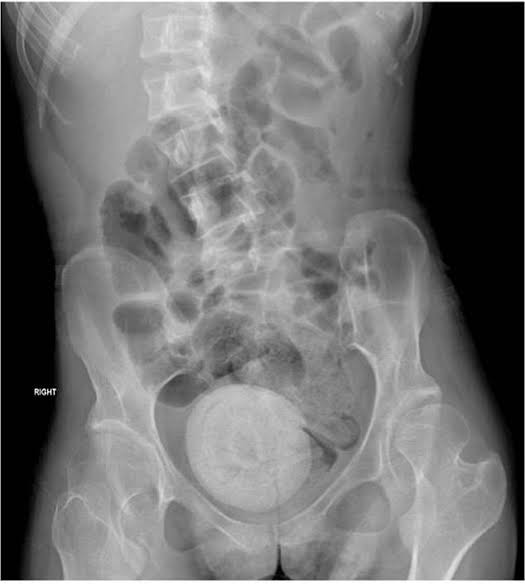

Doctors said she looked pale and lethargic. A CT scan was performed on her abdomen and pelvis, and images showed a large, round mass in her pelvic area.

Because the stone was so large, it was pressing against the woman’s bladder, which reduced its capacity and led to further leakage of urine.